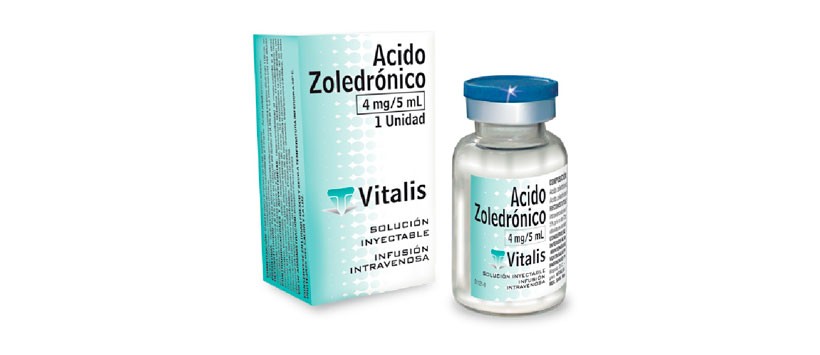

Figura 3: El Zolendronato o ácido Zolendrónico, es el bifosfonato más utilizado y es uno de los fármacos que los cirujanos dentistas deben tener siempre presente.